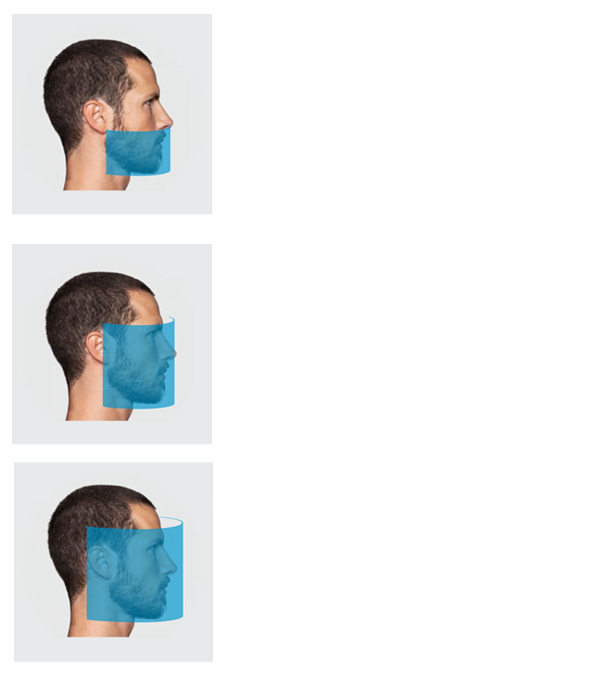

GIANO HR – универсальное обновляемое устройство от NewTom для всех задач, связанных с радиографией. Благодаря полному диапазону опций 2D и 3D исследования для стоматологии оно предлагает множество особых трехмерных обследований для челюстно-лицевой хирургии, оториноларингологии и осмотра шейного отдела позвоночника. Визуализация только наивысшего качества с технологиями и опытом NewTom

- Детектор для конусно-лучевой 3D томографии с размером FOV 16х18 см